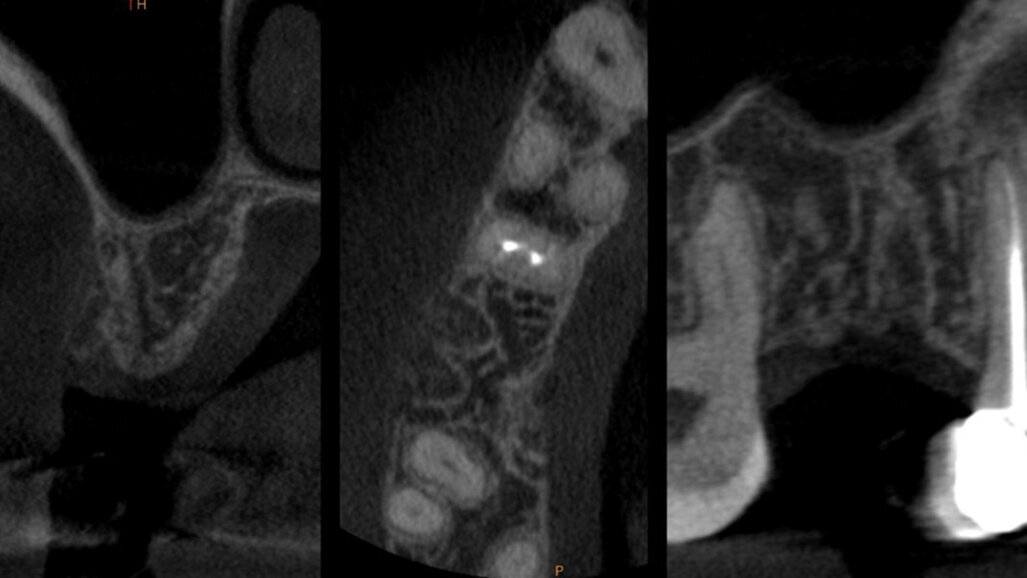

È stata eseguita una CBCT preoperatoria (Figg. 2a, 2b). La paziente, una donna di 52 anni in buona salute, ha iniziato la terapia antibiotica il giorno prima dell’estrazione con 2 gr. Amoxicillina e Acido Clavulanico. Dopo l’anestesia locale, è stata eseguita un’estrazione atraumatica cercando di non danneggiare le corticali ossee. L’alveolo è stato accuratamente pulito e risciacquato con acqua ossigenata e clorexidina 0,2% (Fig. 3). È stata praticata un’incisione intrasulculare sull’aspetto vestibolare dell’alveolo estrattivo, estendendosi al centro dei denti adiacenti. Un lembo a tutto spessore è stato sollevato ed il periostio staccato con micro-scollatori ha permesso di creare una busta per la lamina corticale (Fig. 4). La lamina corticale soft da 0,5 mm è stata prima idratata per cinque minuti in soluzione sterile e poi tagliata nella forma desiderata, tra 8 e 10 mm di altezza e con un’estensione che copre i margini mesiali e distali dell’alveolo estrattivo. La lamina corticale può essere facilmente inserita nel sito ed eventualmente ritagliata fino ad ottenerne un perfetto adattamento. I bordi devono essere rifiniti con angoli arrotondati per ridurre il rischio di perforazione e/o deiescenze sul versante vestibolare. La colla di fibrina umana (Tisseel, Baxter) è stata diluita al 10% mediante 0,9 ml di acqua bidistillata. Sulla lamina corticale sono state applicate due o tre gocce di colla, dopo di che la lamina è stata poi schiacciata con una gentile pressione digitale per adattarsi alla posizione predefinita (Fig. 5). Il lato palatale dell’alveolo è stato invece lasciato guarire per prima intenzione. Una spugna di collagene (Condress, Smith & Nephew) è stata inserita all’interno dell’alveolo per stabilizzare il coagulo ed è stata posizionata una sutura incrociata (4-0 punti di sutura in ptfe) per mantenere la spugna in posizione, le papille sono state invece suturate con due suture a fionda7 (Fig. 6). Quattro mesi dopo l’estrazione, prima di inserire l’impianto, è stata eseguita una CBCT post-operatoria per valutare la guarigione del sito operato.

La CBCT dopo 4 mesi ha mostrato il mantenimento della corticale vestibolare (Figg. 7a, 7b), e anche un aumento della dimensione bucco-linguale (Fig. 8). Sul lato palatale, dove il sito è guarito naturalmente, la parete palatale ha subito un normale rimodellamento. Le immagini CBCT mostrano chiaramente la capacità della lamina corticale di inibire il riassorbimento della corticale buccale e di sostituirla o sostenerla. Ciò suggerirebbe che la lamina potrebbe essere utilizzata al posto di una membrana D-PTFE per ottenere un risultato ancora migliore rispetto alla classica tecnica di inibizione periostale, considerando anche che la lamina si integra nel sito8, 9 e non richiede una procedura di rientro. La guarigione è avvenuta senza complicazioni e il volume osseo creato era sufficiente per posizionare un impianto standard da 4,1 mm (Figg. 9, 10).

Figg. 7a, 7b - CBCT dopo Inibizione Periostale Modificata.